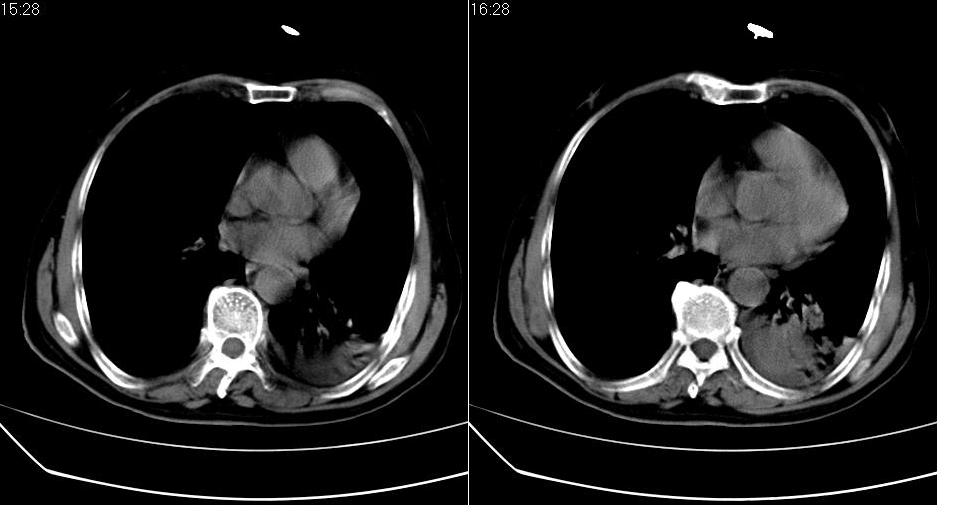

左下肺体积缩小,密度增高,见片增密影。边界模糊,见支气管充气像,肺门纵隔无异示,心脏气管左移,左侧胸腔少量积液。考虑肺部感染伴部分肺不张[有脑梗塞病史坠积性肺炎可能]

1、左肺下叶后基底段炎症并膨胀不全。

2、左侧胸腔积液。

3.两肺慢支改变。

左下肺体积缩小,密度增高,并见大片状致密影,边界模糊,其内见支气管充气像,肺门纵隔无异常,心脏气管左移,左侧胸腔少量积液。考虑:左肺炎性病变伴不张。